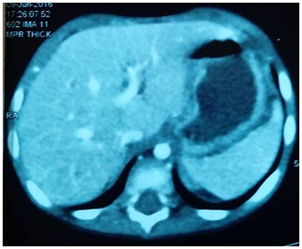

Laboratory investigations revealed low hemoglobin level (Hb=8gm) with mild leukocytosis. Serum electrolytes and coagulation profile were within normal limits. Ultrasound (US) abdomen revealed large intra-peritoneal encysted fluid collection about 8x2x5cm medial to the descending colon with multi-layered wall, turbid content and internal septations. This is associated with multiple mesenteric lymphadenopathy. The mass displaces the descending colon laterally and the small bowel loops, which are seen collapsed, to the right side. CT abdomen with IV and oral contrast revealed a large intra-abdominal cystic lesion about 4x10x10cm abutting aorta, IVC and renal vessels posteriorly denoting a retro-peritoneal origin and displacing the distal duodenum anteriorly and the descending colon postero-lateral. The mass is of inverted C shape with imperceptible wall and turbid content (Figure 1) (Figure 2). Enteric duplication cyst was considered as a main differential and less likely pseudopancreatic cyst. Serum amylase was ordered and revealed to be within normal range.

Figure 1 Coronal CT abdomen revealing inverted C-shape abdominal cystic lesion.

Figure 2 Axial CT abdomen showing imperceptible cyst wall with mildly turbid content.